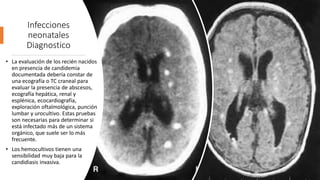

• La evaluación de los recién nacidos

en presencia de candidemia

documentada debería constar de

una ecografía o TC craneal para

evaluar la presencia de abscesos,

ecografía hepática, renal y

esplénica, ecocardiografía,

exploración oftalmológica, punción

lumbar y urocultivo. Estas pruebas

son necesarias para determinar si

está infectado más de un sistema

orgánico, que suele ser lo más

frecuente.

• Los hemocultivos tienen una

sensibilidad muy baja para la

candidiasis invasiva.